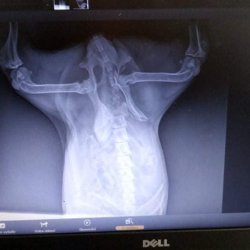

Čertík se zlomenou pánví po sražení autem

Čertík, tak pojmenovaly tety z Dočasek DeDe mladého pejska sraženého u Varnsdorfu. Ležel ve škarpě u silnice, nemohl vstát a naříkal bolestí. Po složitějším odchytu, kdy pejsek kousal díky šoku a bolesti, se podařilo ho dopravit na jedinou veterinu v okolí, kde ho primárně ošetřili a udělali RTG. Bylo zde podezření na trauma páteře, to se však nepotvrdilo, potvrdila se zlomenina pánve. Po převozu na pražskou kliniku mu byla odebrána krev, udělalo se sono vyšetření. Veterináři se rozhodli pro okamžitou revizi břišní dutiny. Pravděpodobně při nárazu autem došlo k utržení močovodů nebo jinému traumatu močových cest a ledviny v důsledku toho selhávaly.